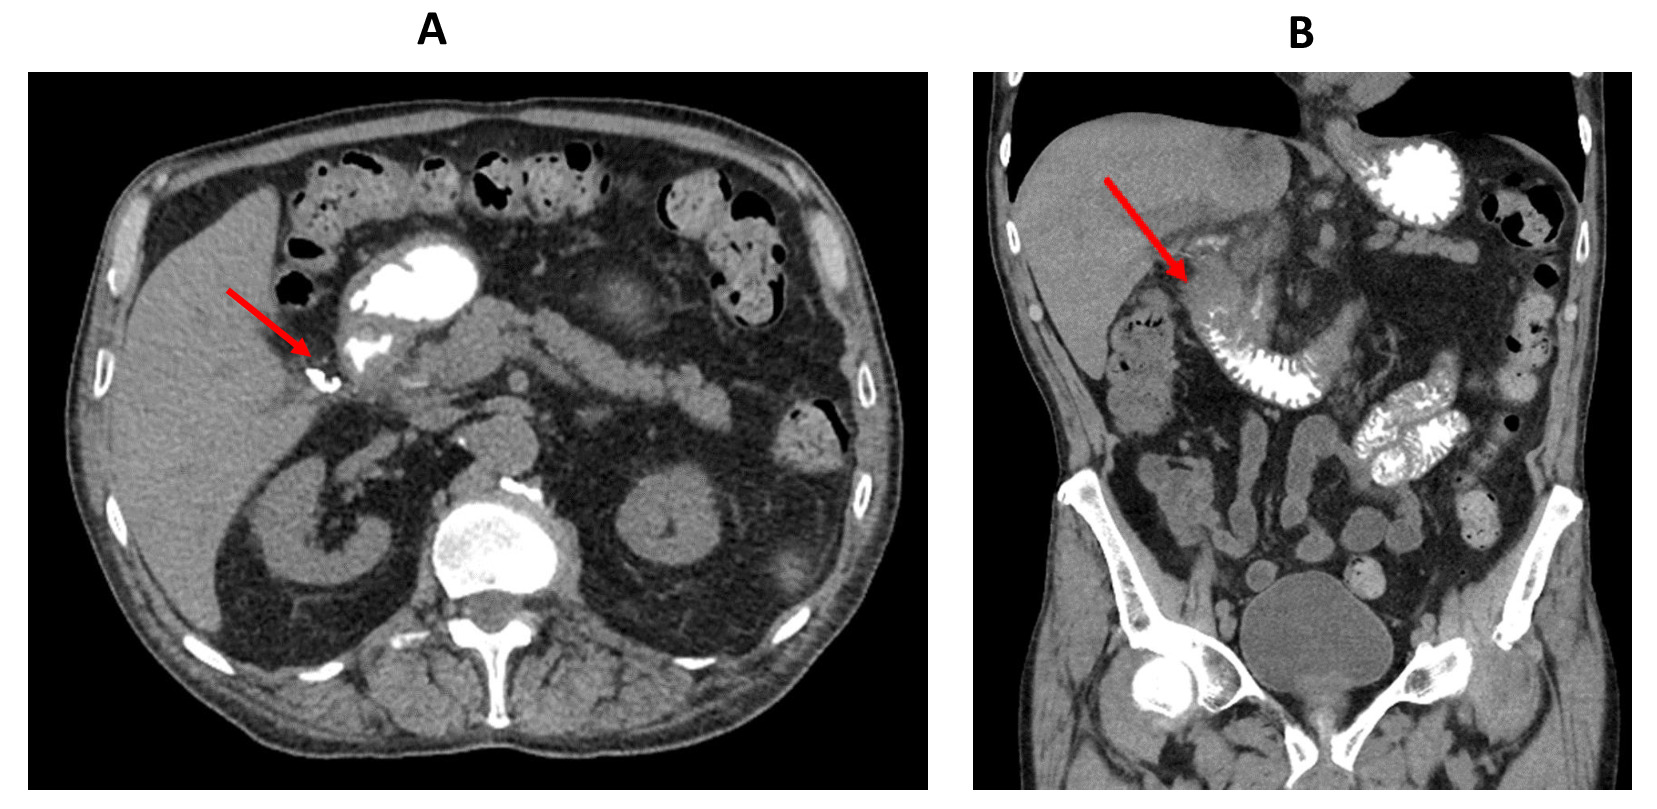

A computed tomography (CT) scan of the abdomen with intravenous and oral contrast obtained in the emergency department showed segmental wall thickening of the second part of the duodenum and duodenal bulb with adjacent fat stranding. There was also a pocket of gas in the medial aspect of the duodenum which was filled by extravasated oral contrast suggesting a contained duodenal ulcer perforation. (Figure 1).

_axial_ct_scan_of_the_abdomen_showing_extravasated_oral_contrast_outside_the_duodenum_(.png)